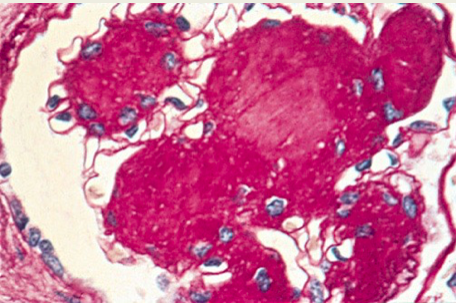

Diabetic GN on PAS

• Thickened GBM w/ nodular glomerulosclerosis